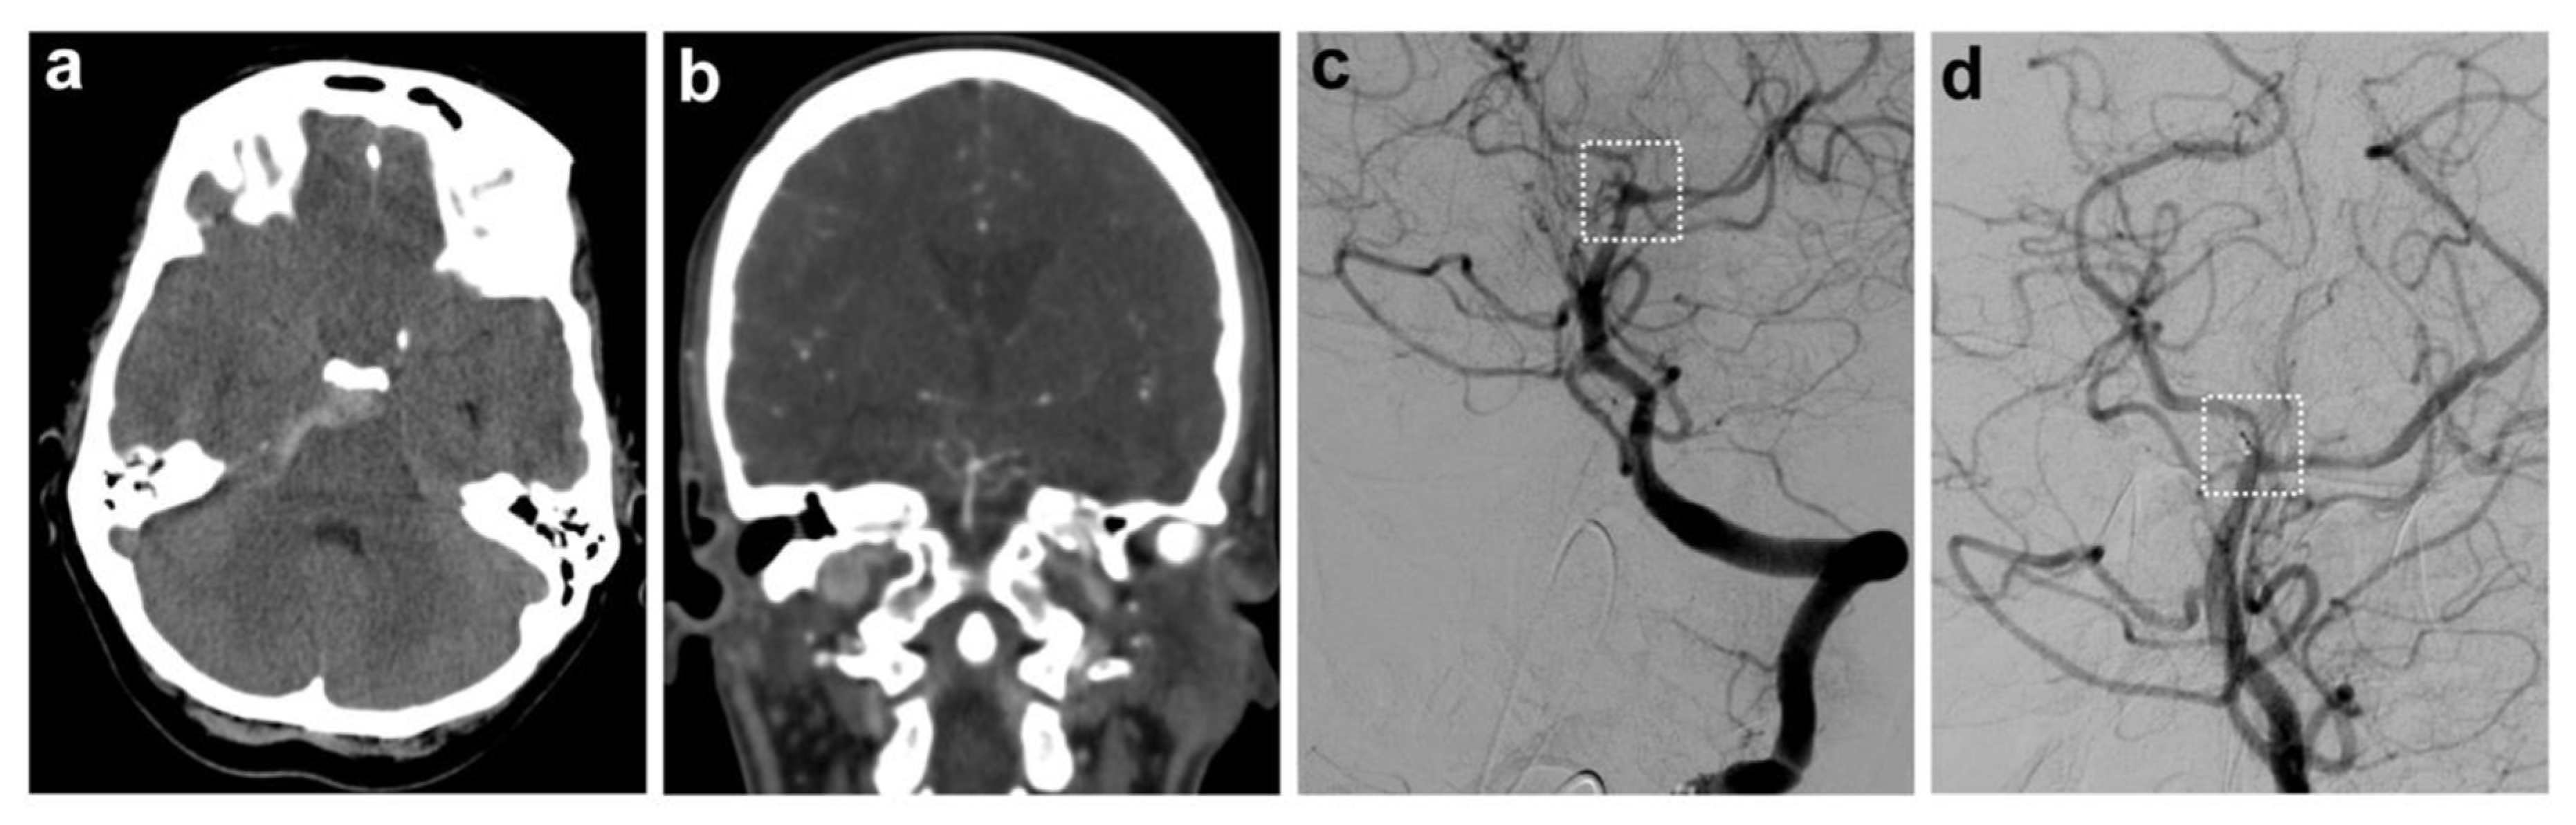

Of the 77 patients, 7 (9.1%) were found to have an aneurysm, while 70 (90.9%) had no aneurysmal pathology (exemplary case: Figure 1). In this cohort, initial CTA—performed prior to DSA—identified only 57% of aneurysms (i.e., 4/7 cases). All aneurysms were found in the posterior circulation, originating from small cerebellar arteries, with a maximum diameter of 3 mm.

Figure 1.

Exemplary case of a patient with a perimesencephalic bleeding pattern and an aneurysmal pathology. (a) Non-contrast CT depicting a perimesencephalic pattern of subarachnoid hemorrhage with predominantly right-sided distribution. (b) Subsequent CT angiography with evidence of a tiny saccular aneurysm of the SCA on the right, which was initially thought to be a prominent basilar artery. (c) DSA confirmed the aneurysm of the right SCA; (d) shows the coiled aneurysm (marked with a white dashed box).